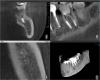

Уважаемые спеиалисты, помогите, пожалуйста, советом по моей ситуации. Около полугода назад заменила старую пломбу на 37 зубе, который был витальный и никогда не беспокоил. После этого наблюдались боли при накусывании, а где-то через пару месяев начались ощущения повышенной температуры в районе корней этого зуба. Многократно обращалась к разным врачам с этими жалобами. В результате заменили вновь пломбу, просила депульпировать - отказали ,поскольку не нашли показаний. Неприятные ощущения становились сильнее. Месяц назад я настояла на депульпировании, но ощущения остались прежние. Множество снимков показывало, что у меня всё гуд. Пока на днях не сделала КТ, которая показала, что мне, со слов моего ортопеда, не прошли устье и пробили корень. На верхушке образовалась киста, которая, как мне сказали пока не капсулизировалась. Вопрос в следующем - на сколько реально переличить этот корень? В случае удачной распломбировки, прочистки устья, дезинфекии стоит ли сразу запломбировывать или правильнее ходить некторое время с лекарством?

post-12053-1280854012_thumb.jpg